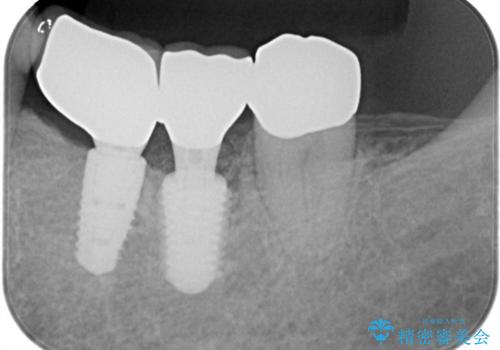

歯の保存は困難と診断しインプラントで治療を行いました。1Dayインプラントの適応だったので、抜歯した当日にインプラントを埋入しました。

1Dayインプラントは低侵襲なので痛みもほとんどありません。従来のインプラント治療だと1年弱かかるのが、3ヵ月で治療を終える事が出来ました。

術後痛みも無く、3ヵ月で治療を終える事が出来ました。